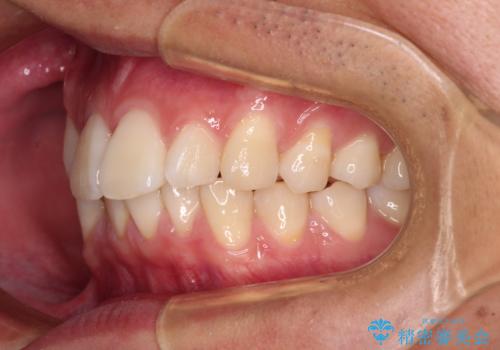

前歯のデコボコをインビザラインで綺麗に改善

- 上下前歯のデコボコとクロスバイトを気にして来院された患者様です。

インビザラインを用い、IPR(歯と歯の間を削る)と歯列全体を拡大させることで、歯並びを整えていくこととしました。

毎日22時間の装着時間を徹底してくださったのですが、左右ともに臼歯が咬合しなくなるという、インビザライン独特の症状が強く長く続いてしまい、終了するまでに長期間を要してしまいました。